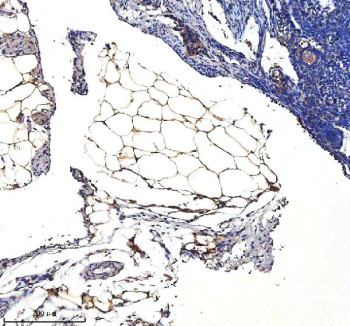

Adding 0.2 ml of distilled water will yield a concentration of 500 ug/ml. SERPINA12 antibody detects Vaspin (serpin A12), a secreted serine protease inhibitor that modulates insulin sensitivity, inflammation, and metabolic balance. Encoded by the SERPINA12 gene on chromosome 14q32.13, this protein belongs to the serpin (serine protease inhibitor) superfamily, known for their roles in controlling proteolytic cascades. Vaspin is predominantly expressed in visceral adipose tissue, liver, and pancreas, and circulates as an adipokine that improves insulin sensitivity and exerts anti-inflammatory effects. Its expression is influenced by obesity, metabolic stress, and insulin signaling, suggesting a compensatory role in metabolic homeostasis.SERPINA12 inhibits proteases that degrade insulin-sensitizing factors and inflammatory mediators, contributing to glucose regulation and vascular protection. Experimental models demonstrate that Vaspin administration improves glucose tolerance and reduces insulin resistance in obese and diabetic subjects. Mechanistically, it modulates serine protease activity in adipose tissue and the liver, attenuating inflammatory cytokine production and endothelial dysfunction. It may also interact with GRP78 on cell surfaces to activate downstream signaling that promotes insulin sensitivity and cellular protection.The SERPINA12 antibody is widely used in endocrinology, metabolism, and cardiovascular research to study the regulation and function of Vaspin. Western blot analysis typically identifies a 45 kilodalton band corresponding to the unglycosylated form of the protein, while immunohistochemistry shows cytoplasmic and extracellular staining in adipose and hepatic tissues. This antibody supports investigation of the molecular mechanisms underlying insulin resistance, obesity, and metabolic inflammation.Beyond metabolic regulation, SERPINA12 is associated with cardiovascular protection through inhibition of vascular inflammation and endothelial apoptosis. It may also have roles in tissue repair and cancer progression. NSJ Bioreagents provides the SERPINA12 antibody validated for its applications, ensuring accurate detection for metabolic and protease regulation studies.